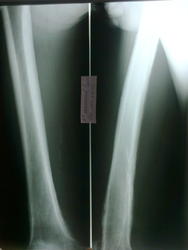

Здравствуйте, коллеги. Помогите с диагностикой. Больной 1954 г.р. пришел от врача-терапевта с направлением "остеоартроз левого коленного сустава", жалуется на боли, со слов год назад получил травму. Профессия-пастух.

Периостит однозначно есть, а вот разреженность костной ткани в н/3 бедренной  кости мне непонятно. Добавил с архива 2 флюорограммы и сделали Р-гр правой бедренной кости

Имеется поражение всего медадиафиза бедренной кости с переоссальными наслоениями, утолщение кортикального слоя. Наличие очага деструкции в н\3 бедренной кости без четкого контура с наличием остесклеротического вала. По моему увеличение плотности мягких тканей. Округлый дефект? в проекции межмыщелкового возвышения б\б коости с зоной остеосклероза. Первично хронический остеомиелит б\б кости?

Периостоз похож на Бамбергера-Мари, но остеолизиз здесь не укладывается. На фиброзно-кортикальный дефект не очень тянет (хотя в много ходящего пешком пастуха может быть). Остеолитические метастазы, скорее. Полный онкопоиск. РГ ОГК обязательно.

А кости таза зачем? В свете только что прочитанного по ссылкам) - может быть периостальная реакция является следствием нагрузки на кости, а литические изменения действительно похожи на метастазы

обязательно вторую ногу... а так пока на зло тянет..